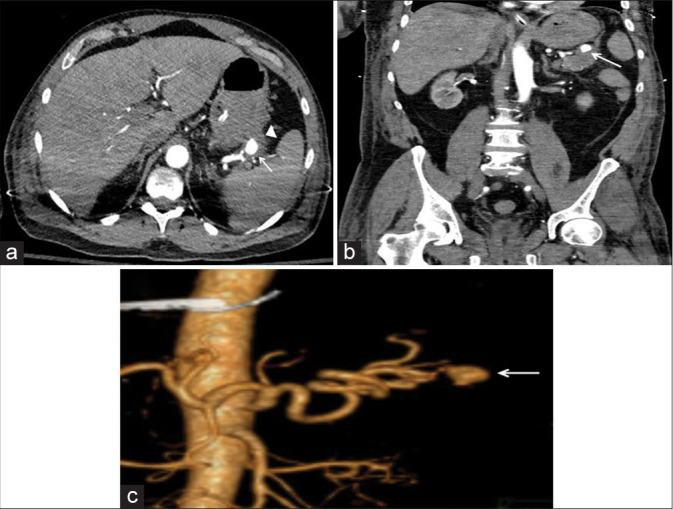

绝大多数因危重消化道出血(GIB)而入住重症监护室(ICU)的患者都有可预测的病因。一旦出血部位被定位在上消化道或下消化道,通常遇到的病因就非常有限。在极少数情况下,需要重症监护病房治疗的 GIB 的病因并非标准考虑因素之一,这可能会导致诊断和治疗延误。在很短的时间内,我们医院的内科重症监护室就收治了三名患者,每名患者的 GIB 病因都出乎意料。这三个病例都产生了各种具有启发性的图像,本系列文章将用这些图像来说明这些病症以及放射科在其评估和管理中的作用。

The great majority of patients admitted to the intensive care unit (ICU) for critical gastrointestinal bleeding (GIB) will have a predictable etiology. Once the site is localized to the upper versus the lower gastrointestinal tract, the number of typically encountered etiological possibilities is quite limited. On rare occasions, the cause of GIB requiring ICU care is not one of the standard considerations, potentially leading to diagnostic and therapeutic delays. Within a short time period, three patients were admitted to our institution's medical ICU each with a different unexpected cause of GIB. All three cases generated a variety of instructive images, which are used in the present series to illustrate these conditions and the role of radiology in their evaluation and management.